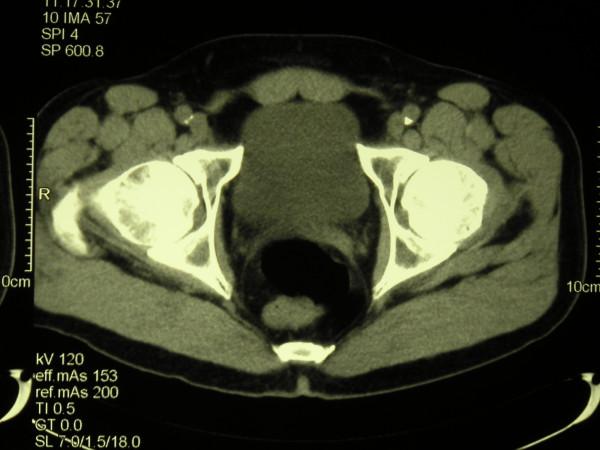

We present a case report of testicular seminoma in a 56 year old man with previously unreported histological findings. In this case seminoma tumour cells did not appear to have spread by the expected lymphatic route. There was no involvement of retro-peritoneal para-aortic lymph nodes. The tumour appeared to have spread directly along the vas deferans in the sub epithelial plane to the mesenteric lymph nodes.

我们报告一例56岁男性睾丸精原细胞瘤病例,具有此前未报道的组织学发现。在此病例中,精原细胞瘤肿瘤细胞似乎未按预期的淋巴途径扩散。腹膜后腹主动脉旁淋巴结未受累。肿瘤似乎是沿输精管在黏膜下层平面直接扩散至肠系膜淋巴结。

结论

这种类型的精原细胞瘤肿瘤扩散此前未被描述过,也不是精原细胞瘤公认的转移途径。在此病例中宏观临床表现为肿瘤标志物正常的I期肿瘤。然而,基于组织学和CT影像学检查结果,肿瘤的病理分期出人意料地升至III期。我们展示了这些不寻常的组织学发现。鉴于这一不寻常的组织学发现,我们强调准确分期以及在靠近腹股沟深环处切除精索的必要性。准确分期对于精原细胞瘤的治疗规划和随访至关重要,并决定预后。